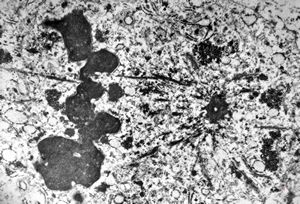

F,76y. | intranuclear needle-like structures - rhabdomyoma,tongue

F,76y. | intranuclear needle-like structures - rhabdomyoma,tongue